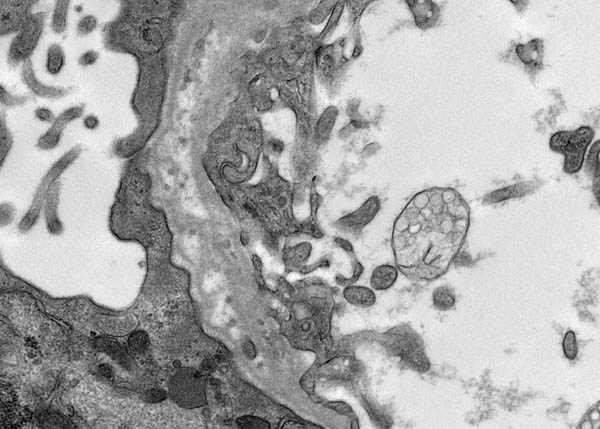

Electron microscopy showed unusual filiform projections of the glomerular basement membrane. These were fewer and longer than the spikes typically seen in membranous nephropathy (Fig. 2). There were also localised areas of glomerular basement membrane lamellation with electron-lucent areas and small electron dense granules (Fig. 3). There was extensive epithelial foot process effacement with microvillous transformation of podocytes. No electron-dense immune complex-type deposits were identified.